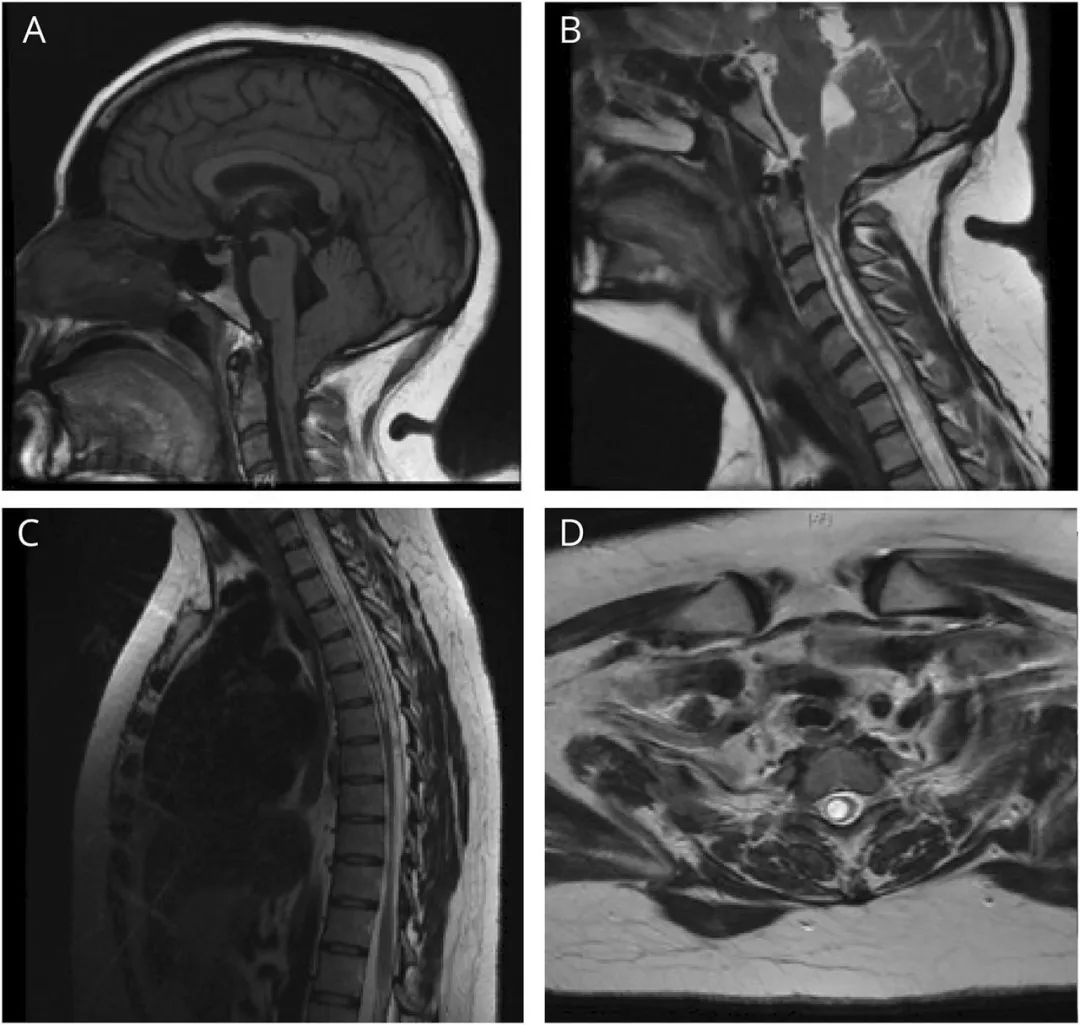

头颅MRI检查显示在枕骨大孔下方18mm处有明显的扁桃体外翻和颈延部背突,考虑为Chiari I型畸形。脊柱MRI显示C2-T6 空洞症(图)。肺功能检查显示限制性疾病模式。多导睡眠图检查显示严重阻塞性睡眠呼吸暂停,呼吸暂停-呼吸不足指数为51。结合病变特点和患者意愿,患者在夜间BiPAP支持下出院。随访时,其呼吸状况保持稳定,但右半身偏瘫并伴有感觉共济失调,需要辅助行走。但随后患者重新考虑手术治疗。

图1 脑和脊柱MRI。(A)头颅MRI的矢状位T1图像显示小脑扁桃体下端疝出枕骨大孔平面18mm、颈延背突、脊髓空洞症,与Chiari I畸形也一致。(B)颈椎MRI的矢状位T2显示鞘内高信号病灶与脊髓空洞一致,从C2水平向下延伸。(C)胸椎MRI的矢状位T2显示鞘内高信号病灶,与脊髓空洞一致,并一直延伸到T6水平。(D)颈椎MRI的轴位T2显示明显扩张的中央管,与脊髓空洞症相一致。 问题思考: 1.呼吸衰竭的病理生理机制是什么? 2.在处理Chiari畸形相关的睡眠呼吸障碍时应考虑哪些因素? 讨论